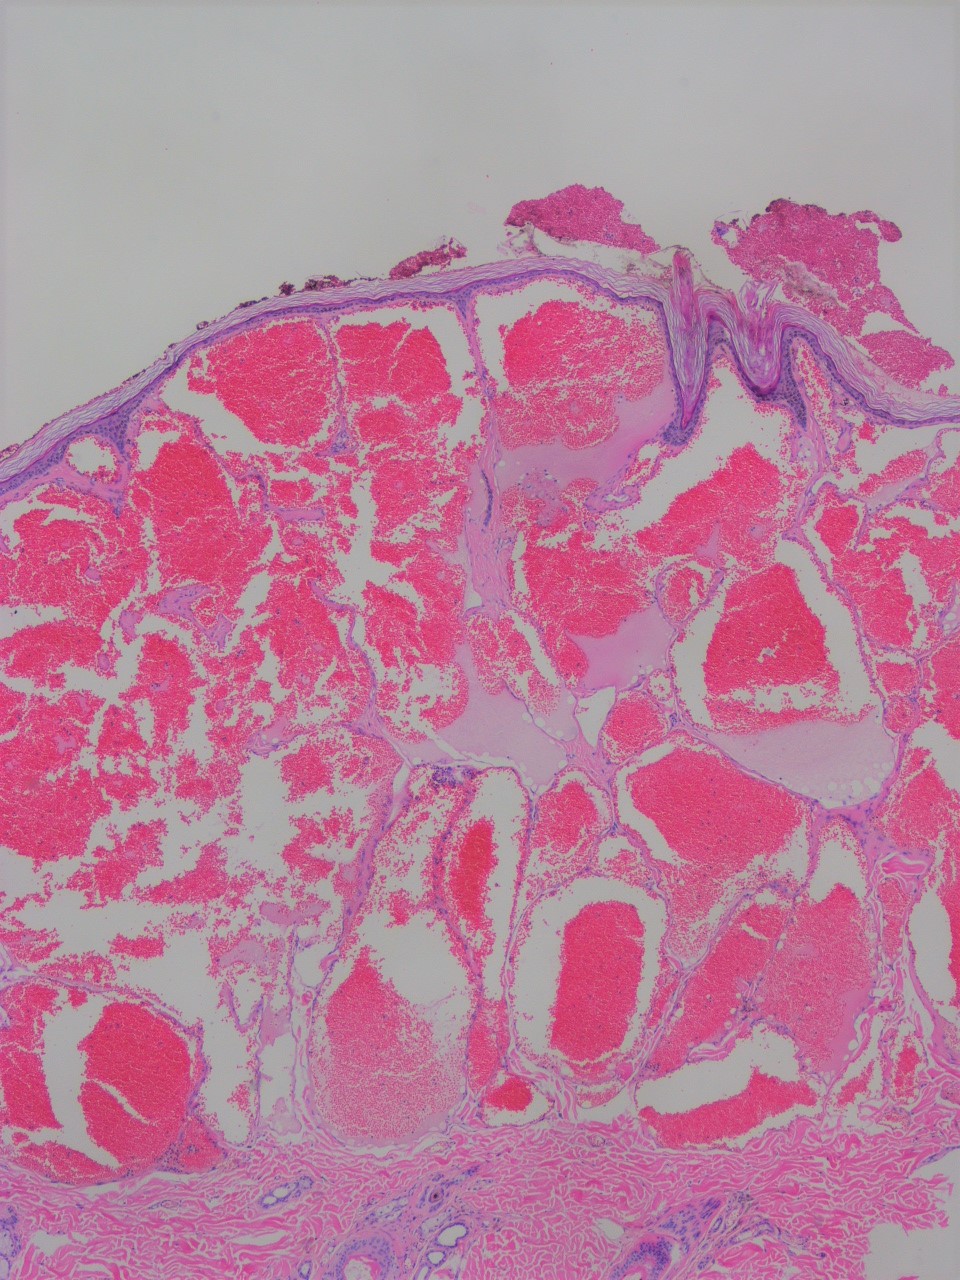

超音波検査(肝臓②) - たなべ内科クリニック(呉市広本町の。血管腫・血管奇形 ー診断と治療についてー | 横浜市立大学附属病院。03202608.jpg。他にも多数、出品しています♪よければ覗いてください☆#サクラBooks【商品について】・送料無料・即購入OK(コメント不要)・中古品ですが、通読に支障のない良好な状態です・書き込み無し・ご購入から1~2日以内に発送いたします・画像に掲載がない場合、付属品は無いものとお考えください・状態は画像にてご確認ください。血管腫 - Wikipedia。※写真と実物で色味に若干の差が出る場合がございます※本のコンディションは中身の状態を重視して判断しております。薬屋のひとりごと 1~13巻(11、12巻ドラマCD付限定特装版)。軽度のスレやキズなどの外装ダメージは記載・掲載を省略しています【ご確認事項】 •申し訳ありませんが、お値下げ交渉には対応しておりません。岩波文庫 三国志 全10巻 オリジナルパラフィン 赤帯付属 各種栞付きです。。•商品価格は、送料や手数料、メルカリ相場などを考慮し、あらかじめご検討いただきやすい金額で設定しております•お値段に関するコメントは削除させていただく場合がございます•価格は定期的に見直しておりますので、ご縁を感じていただけた際にぜひご検討くださいませ・商品状態はあくまで出品者の主観によるものです。【ポストカード付き】悪ノ娘 & 悪の大罪 全13巻セット。画像と説明をご確認の上、ご購入ください・発送は沖縄県から行います→ 地域によっては通常より到着にお時間を要することがあります→ 台風の影響で到着まで7~12日かかった事例もあります。宮部みゆき 『ブレイブ・ストーリー』愛蔵版 署名落款。気長にお待ちいただけますと幸いです・匿名配送(追跡・補償あり)でお送りします・ペット・喫煙者のいない環境で保管しておりますその他ご不明な点がございましたら、お気軽にコメントよりご質問ください「刻まれた21センチ 血管腫と共に生きる」玉元 三奈美#玉元三奈美 #玉元_三奈美 #本 #日本文学/評論・随筆